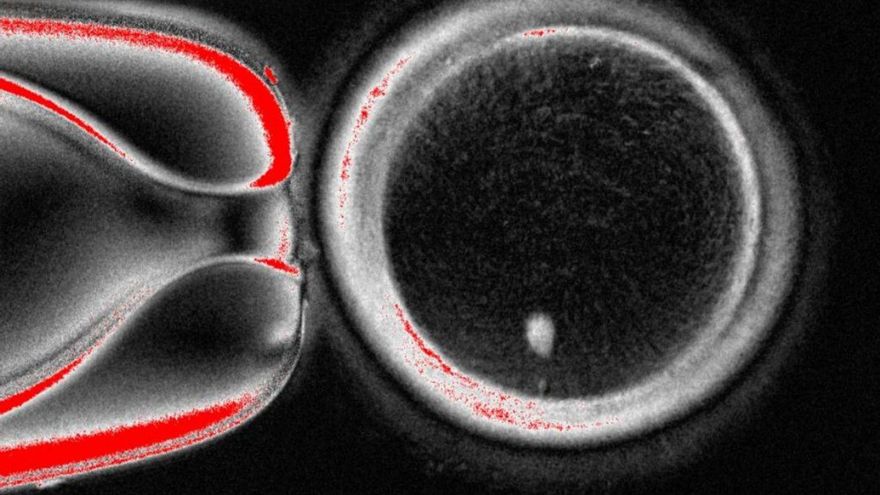

Crearon 82 ovocitos, que luego fueron fertilizados con esperma mediante fecundación in vitro (FIV).

Después de seis días, menos de 9 por ciento de los embriones se desarrollaron hasta el punto en que hipotéticamente podrían ser transferidos al útero en un proceso estándar de FIV.

Sin embargo, los embriones mostraron diversas anomalías, por lo que el experimento fue suspendido.